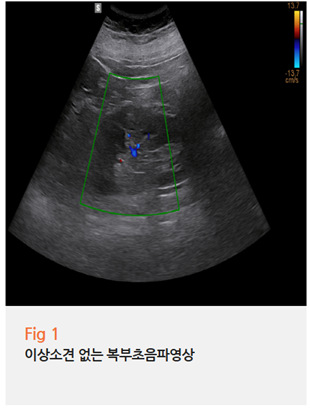

그래서 우선 복부초음파 검사를 진행했습니다.

결과는?

전혀 문제없음

담석 제거는 완벽하게 잘 되어 있었어요.